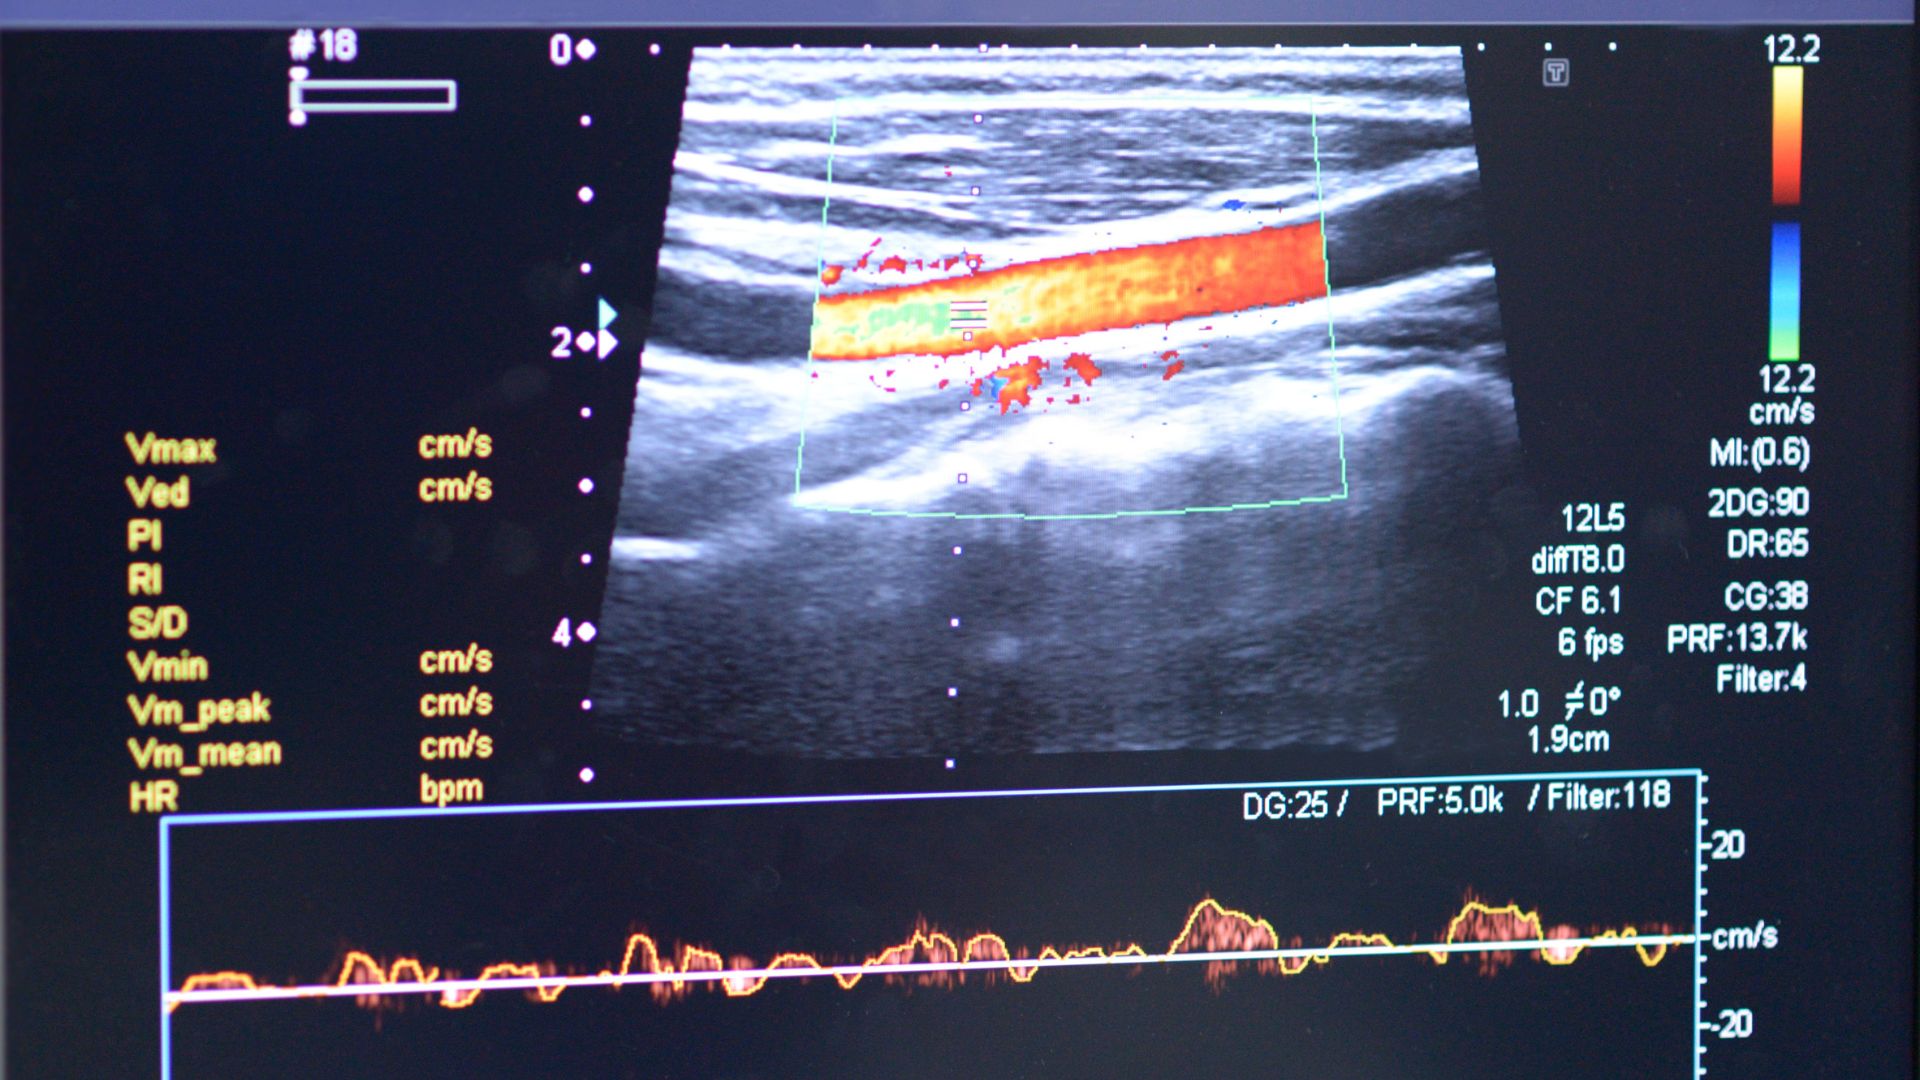

- Siêu âm Doppler mạch máu: Đánh giá bất thường mạch và suy tĩnh mạch, đặc biệt ở chi dưới.